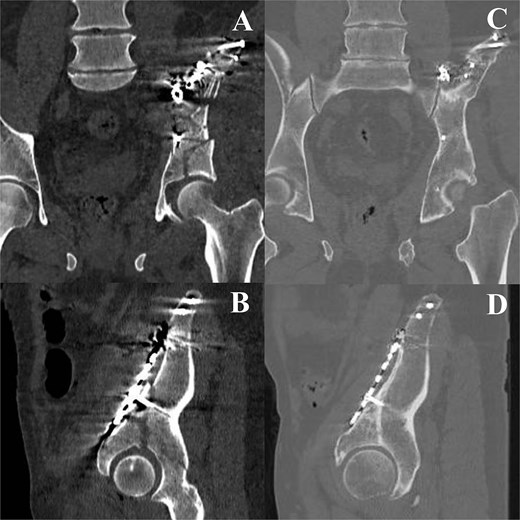

A 58-year-old male presented following a 3-meter fall, with an isolated ABC acetabular fracture of the right side (Fig. 1). Surgery was performed 2 days after the injury using an anterior pelvic approach via the Pfannenstiel incision combined with the first window of the ilioinguinal approach. Fixation began with the iliac crest using 4.5 mm cannulated screws to anchor the constant fragment, followed by a calcaneal plate to address comminution of the iliac wing, and a reconstruction plate for the anterior column (Fig. 2). As the posterior components were well-aligned post-fixation, a posterior approach was deemed unnecessary. Post-operative after 24 months radiographs and TC demonstrated anatomical reduction with no signs of implant failure (Fig. 3), just as shown in the TC comparison (Fig. 4). The physical exam presents a satisfactory range of motion (Fig. 5). Pain, function and quality of life outcomes were assessed using the Visual Analog Scale (VAS), Majeed Pelvic Score, and SF-12 up to 24 months post-operatively, respectively. The results are summarized in the following table (Table 1) and graphic (Fig. 6).

CT immediate postoperative (A, B) comparison with the 24 months follow up (C, D).